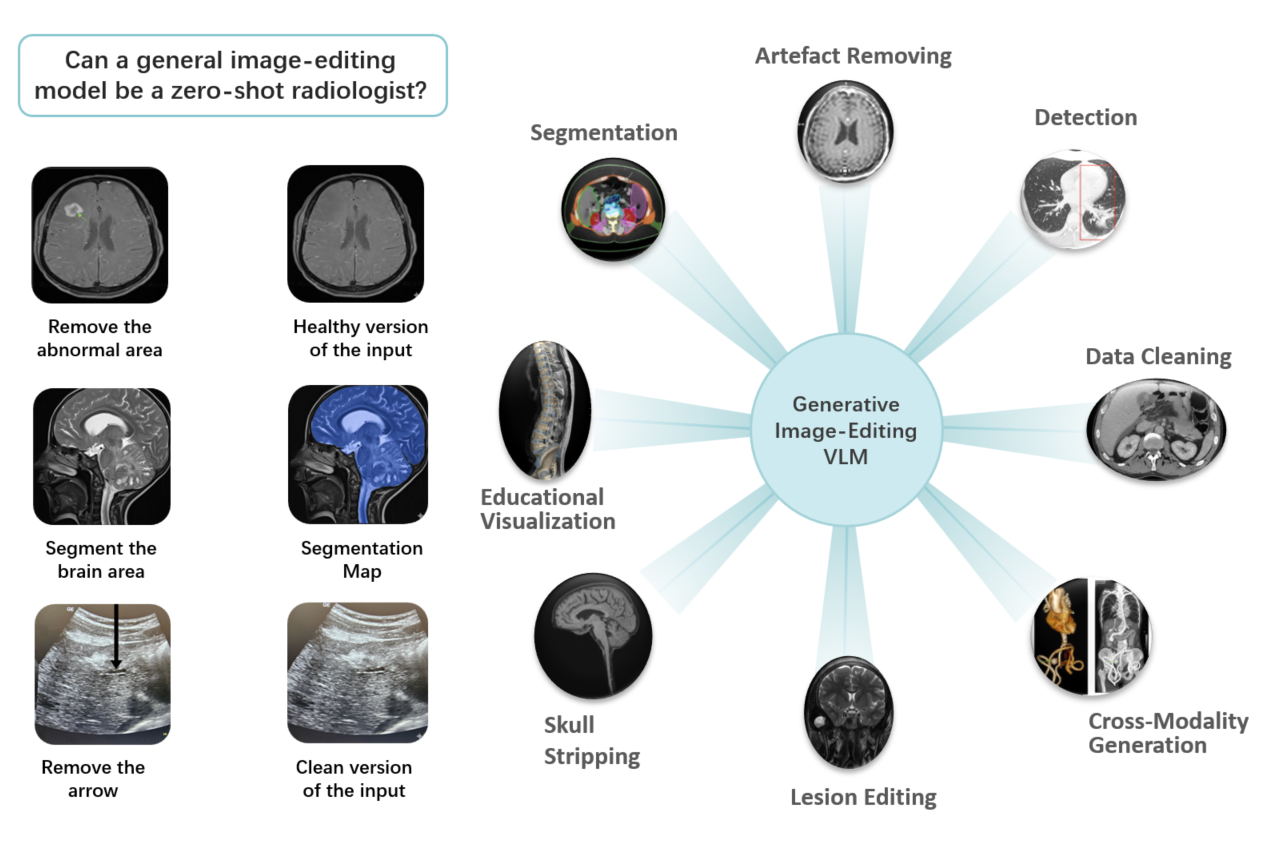

My research focused on the intersection of deep learning and healthcare, particularly in the analysis of medical images. My passion lies in improving the practicality of deep learning algorithms, with a primary focus on Vision and Language models, Cross-Modality Generation, and Multi-Modality Learning. Through my work in these areas, I aim to advance deep learning techniques and their transformative impact on healthcare.

Jun Li, Che Liu, Wenjia Bai, Rossella Arcucci, Cosmin I. Bercea, Julia A. Schnabel.

[paper]

[project]

[huggingface]